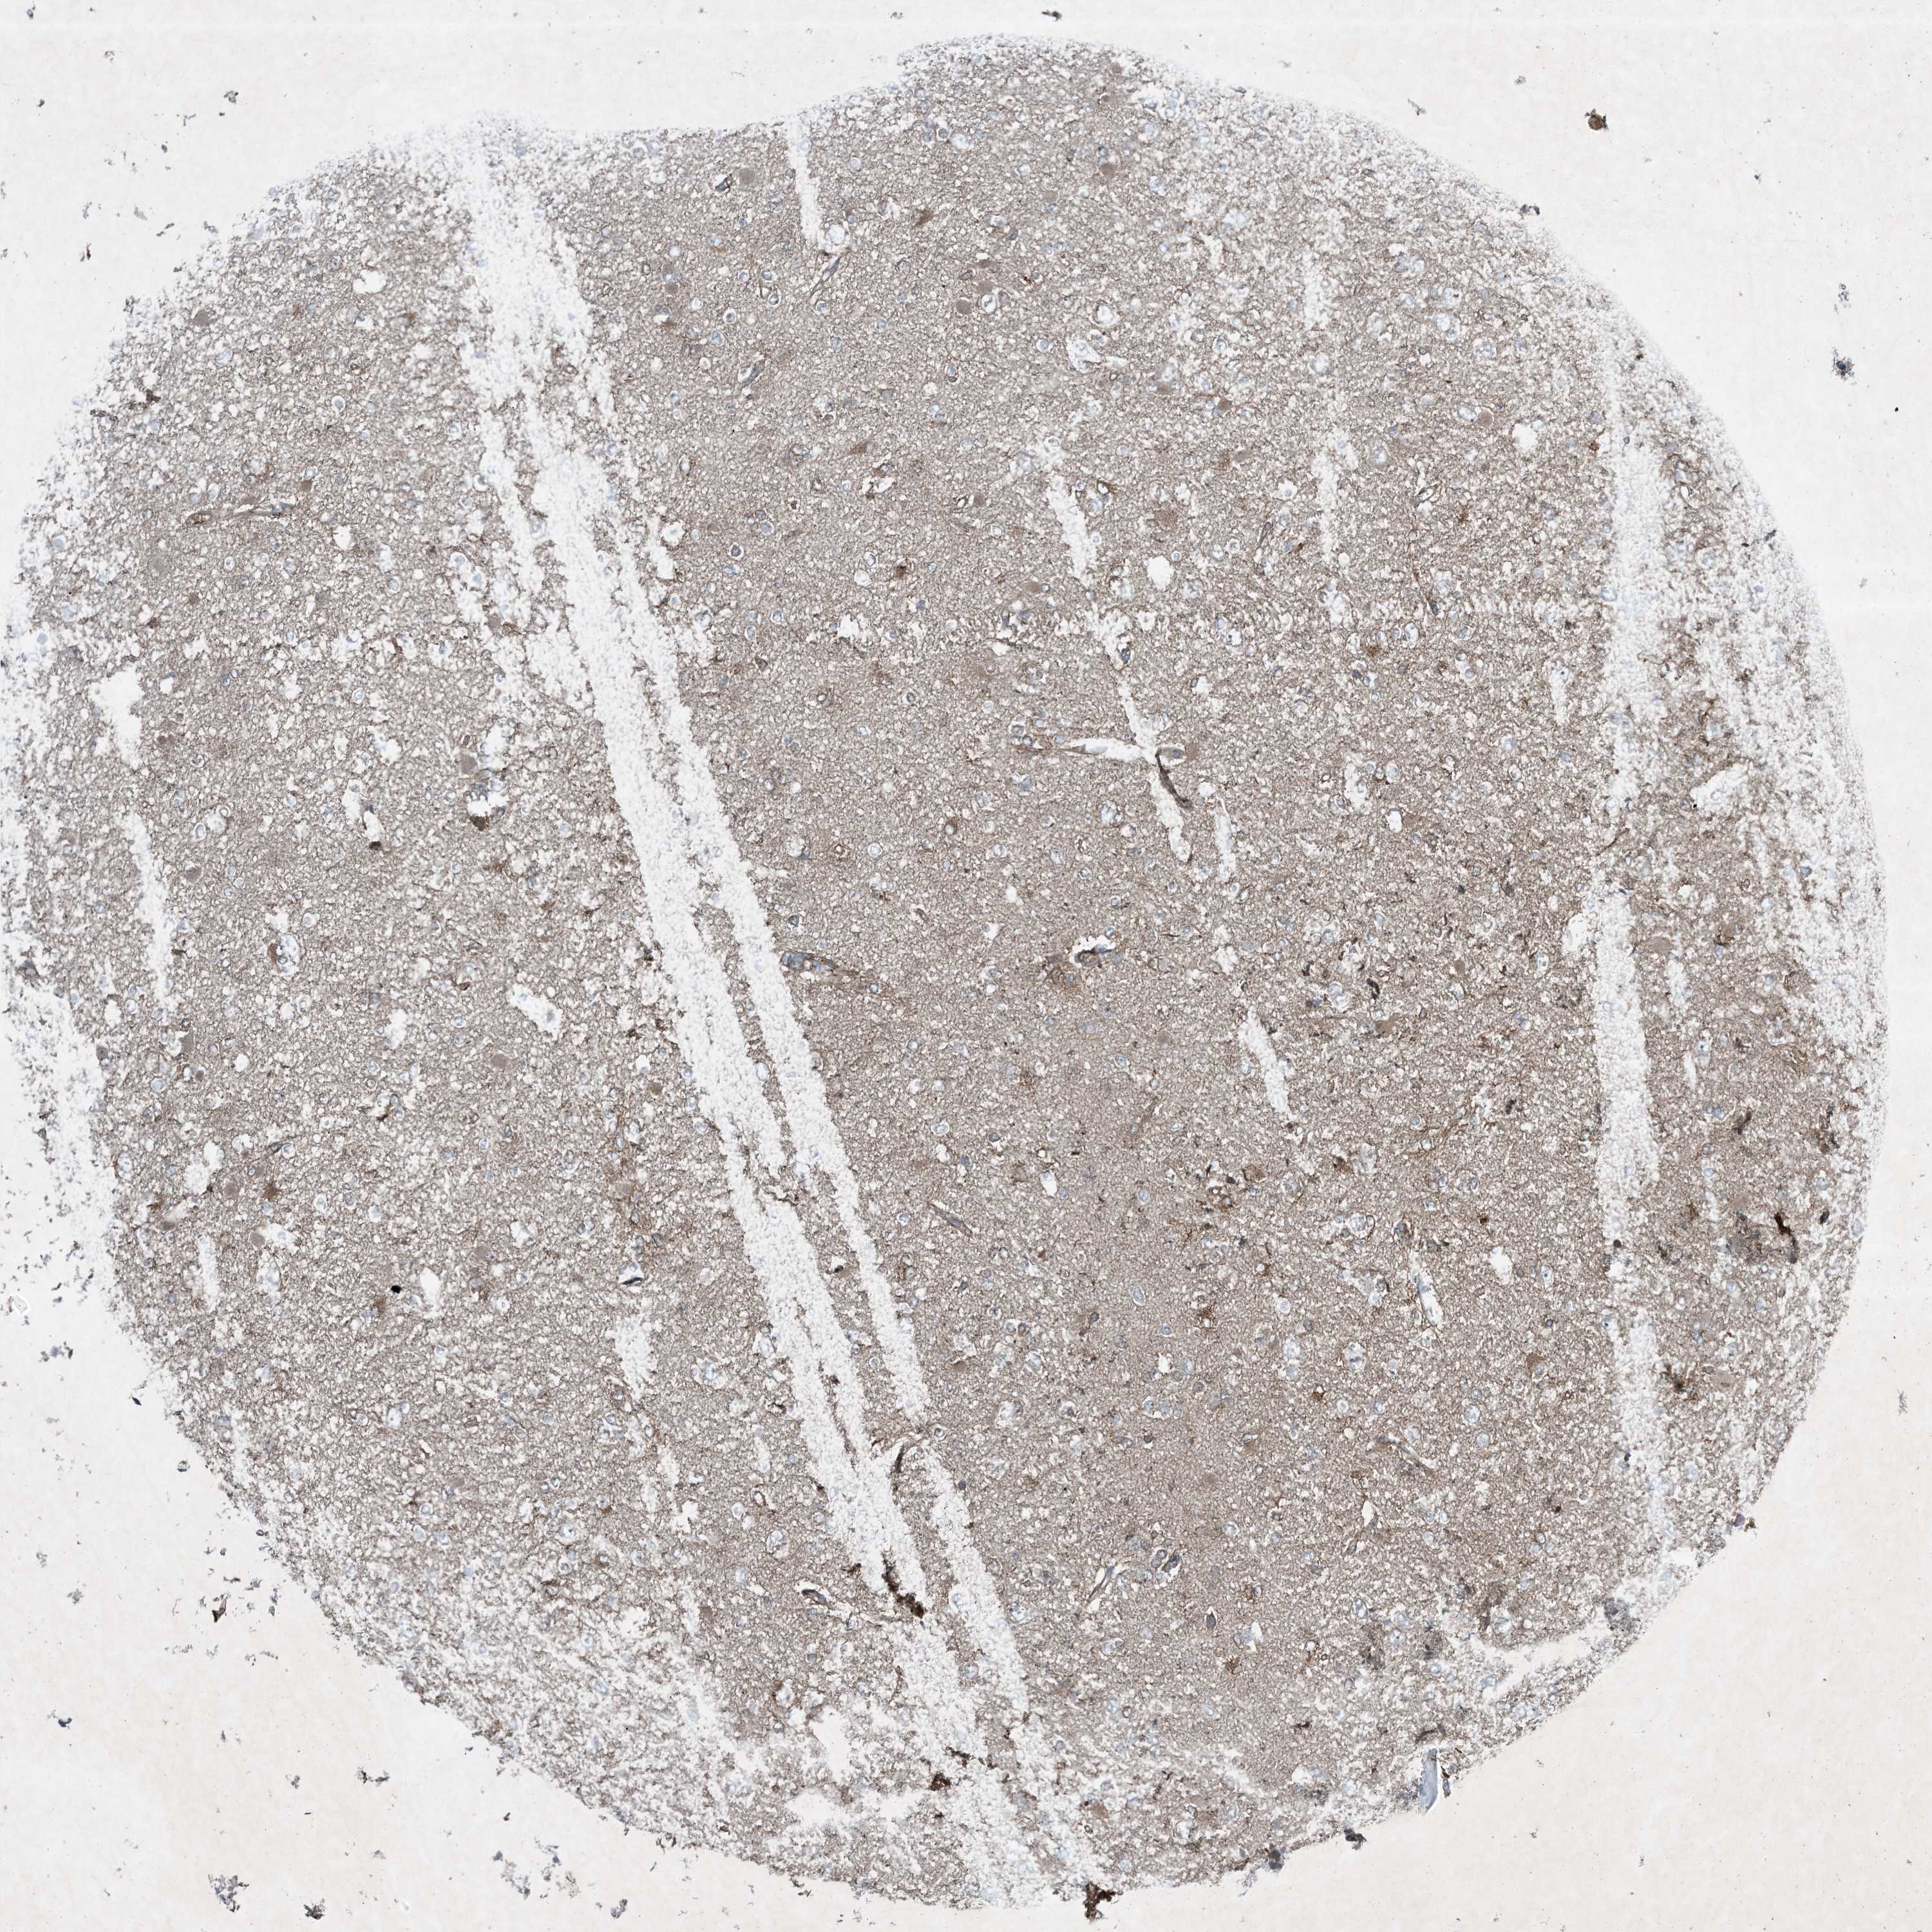

GLIOMA - Protein expressioni

A mouse-over function shows sample information and annotation data. Click on an image to view it in a full screen mode. Samples can be filtered based on level of antibody staining by selecting one or several of the following categories: high, medium, low and not detected. The assay and annotation is described here.

Note that samples used for immunohistochemistry by the Human Protein Atlas do not correspond to samples in the TCGA dataset.

Antibody stainingi

Antibody staining in the annotated cell types in the current human tissue is reported as not detected, low, medium, or high, based on conventional immunohistochemistry profiling in selected tissues. This score is based on the combination of the staining intensity and fraction of stained cells.

Each image is clickable and will lead to virtual microscopy that enables deeper exploration of all samples and also displays staining intensity scores, fraction scores and subcellular localization as well as patient and tissue information for each sample.

Antibody HPA029666

Antibody HPA029667

Antibody HPA029668

Antibody HPA029669

Glioma, malignant, High grade

Glioma, malignant, Low grade

Glioblastoma, NOS